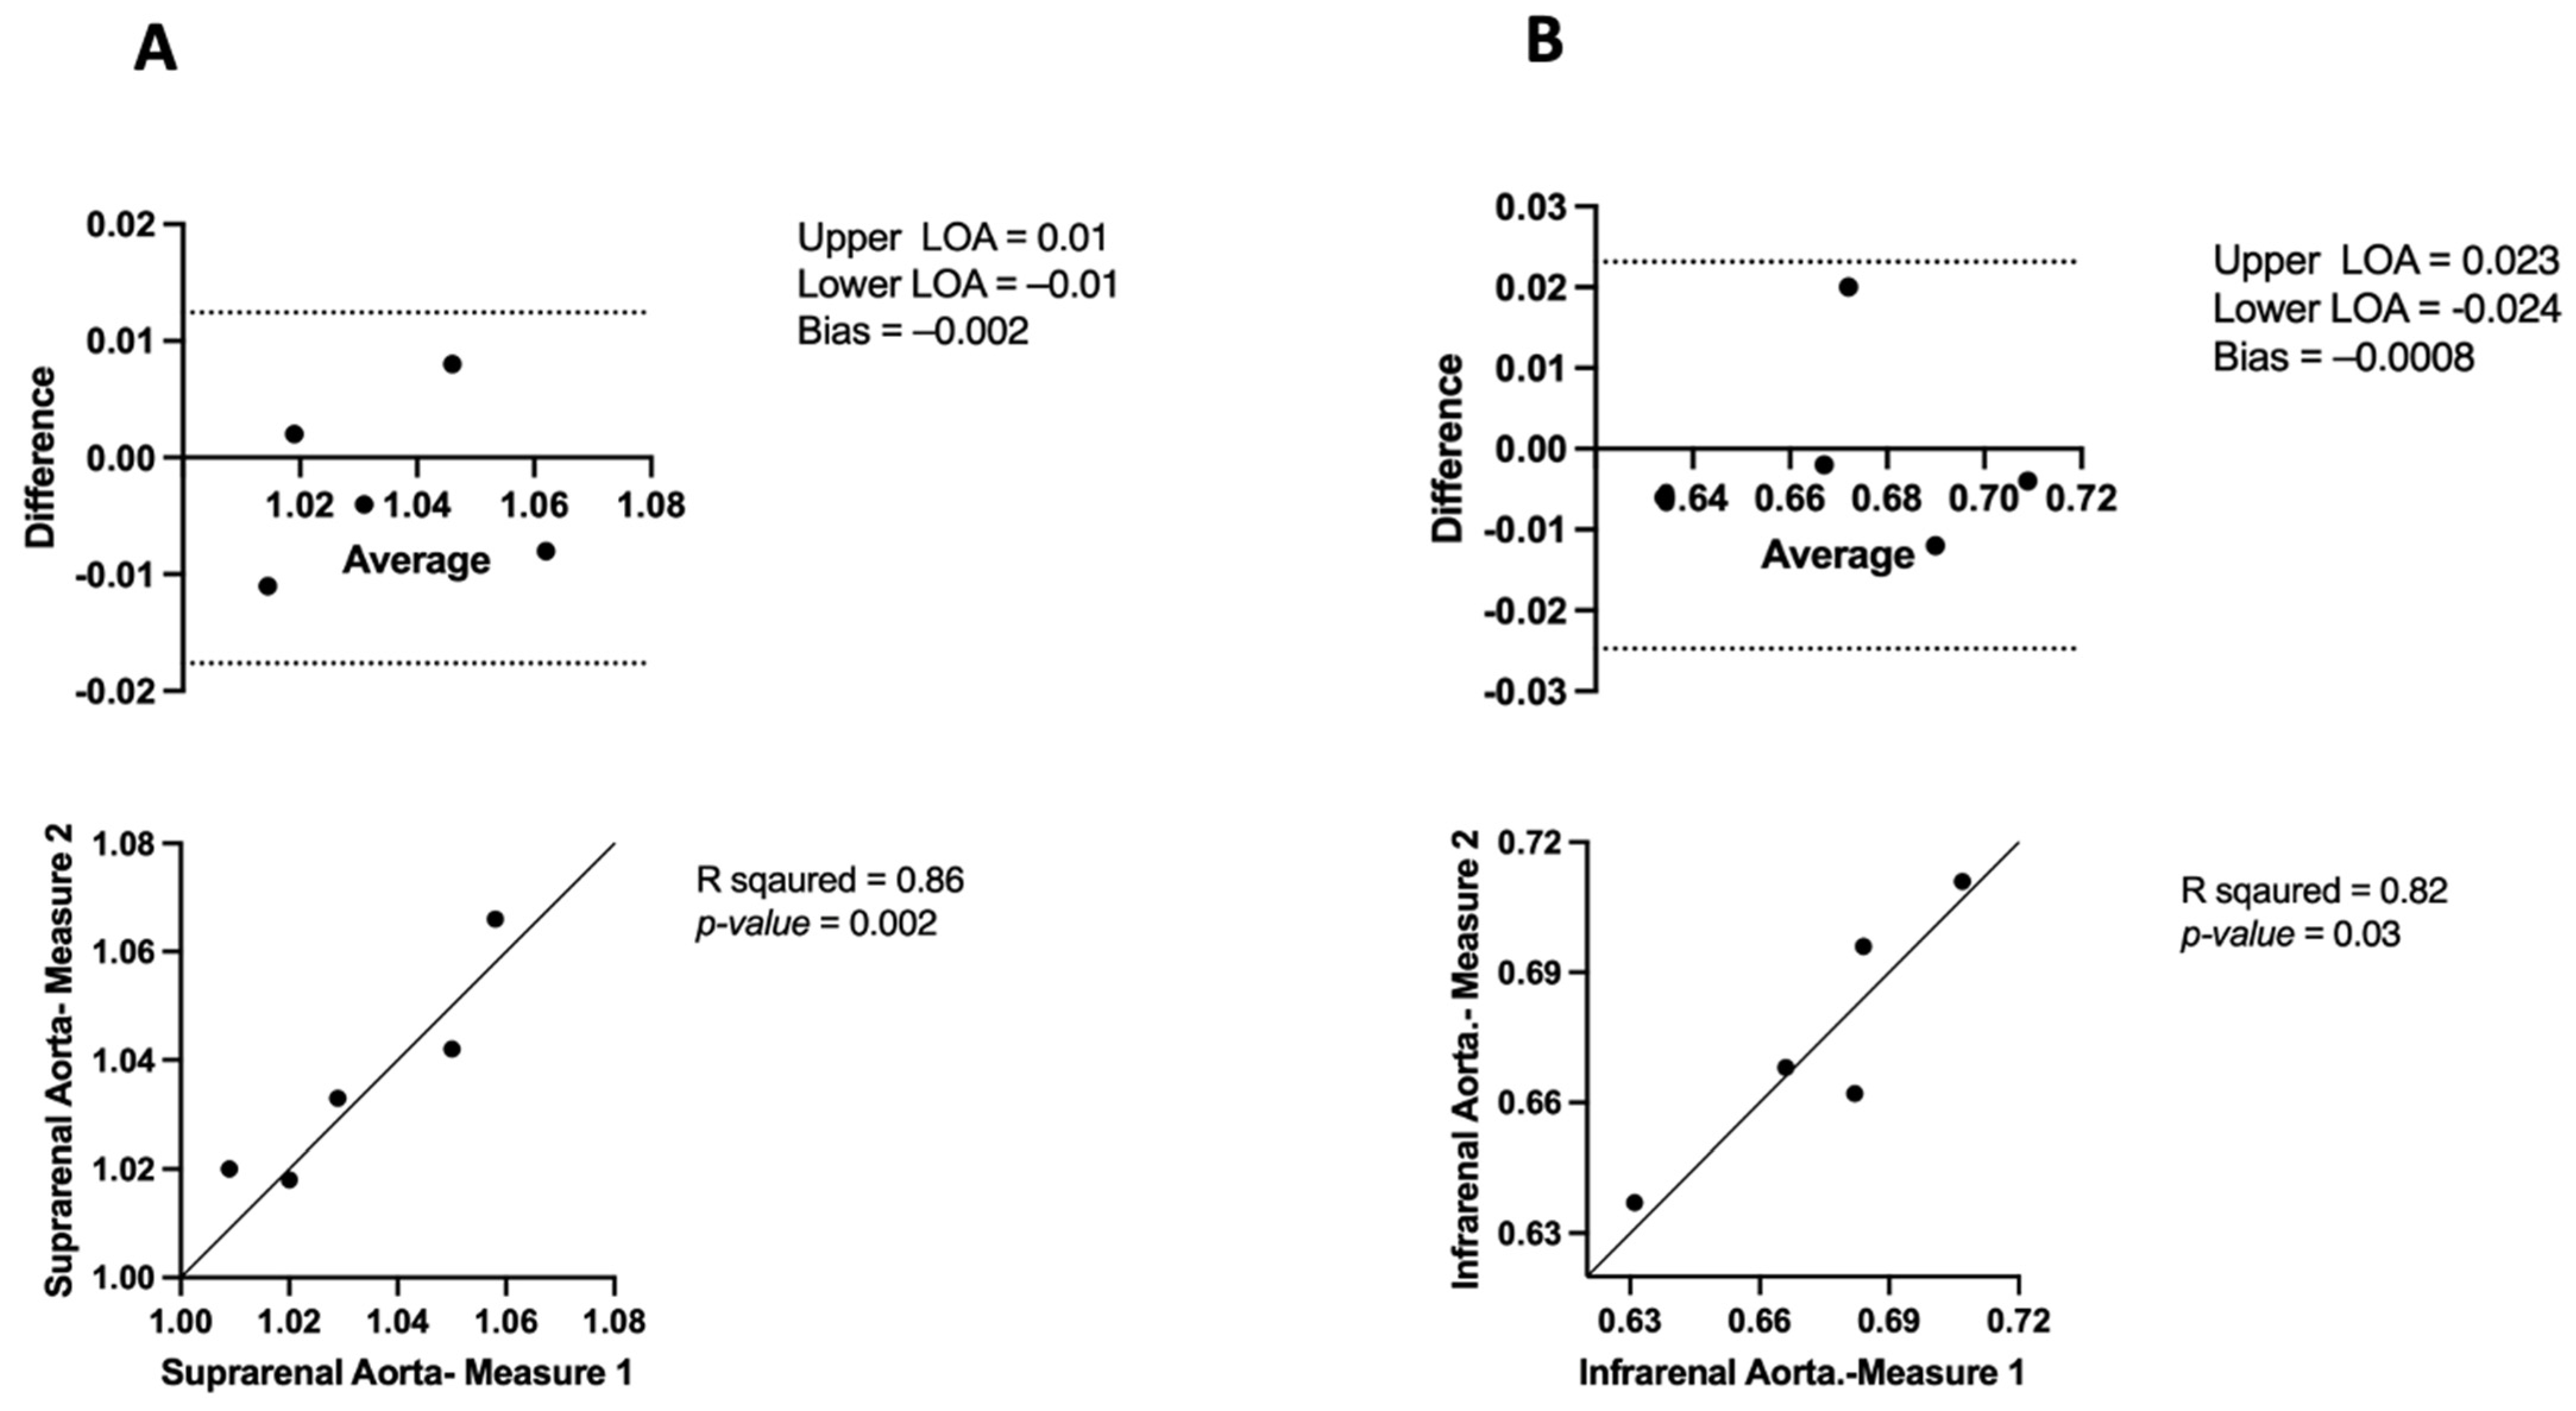

3.1. Inter-Observer and Intra-Observer Variability in μCT

3.1.1. Inter-Observer Variability

3.1.2. Intra-Observer Variability